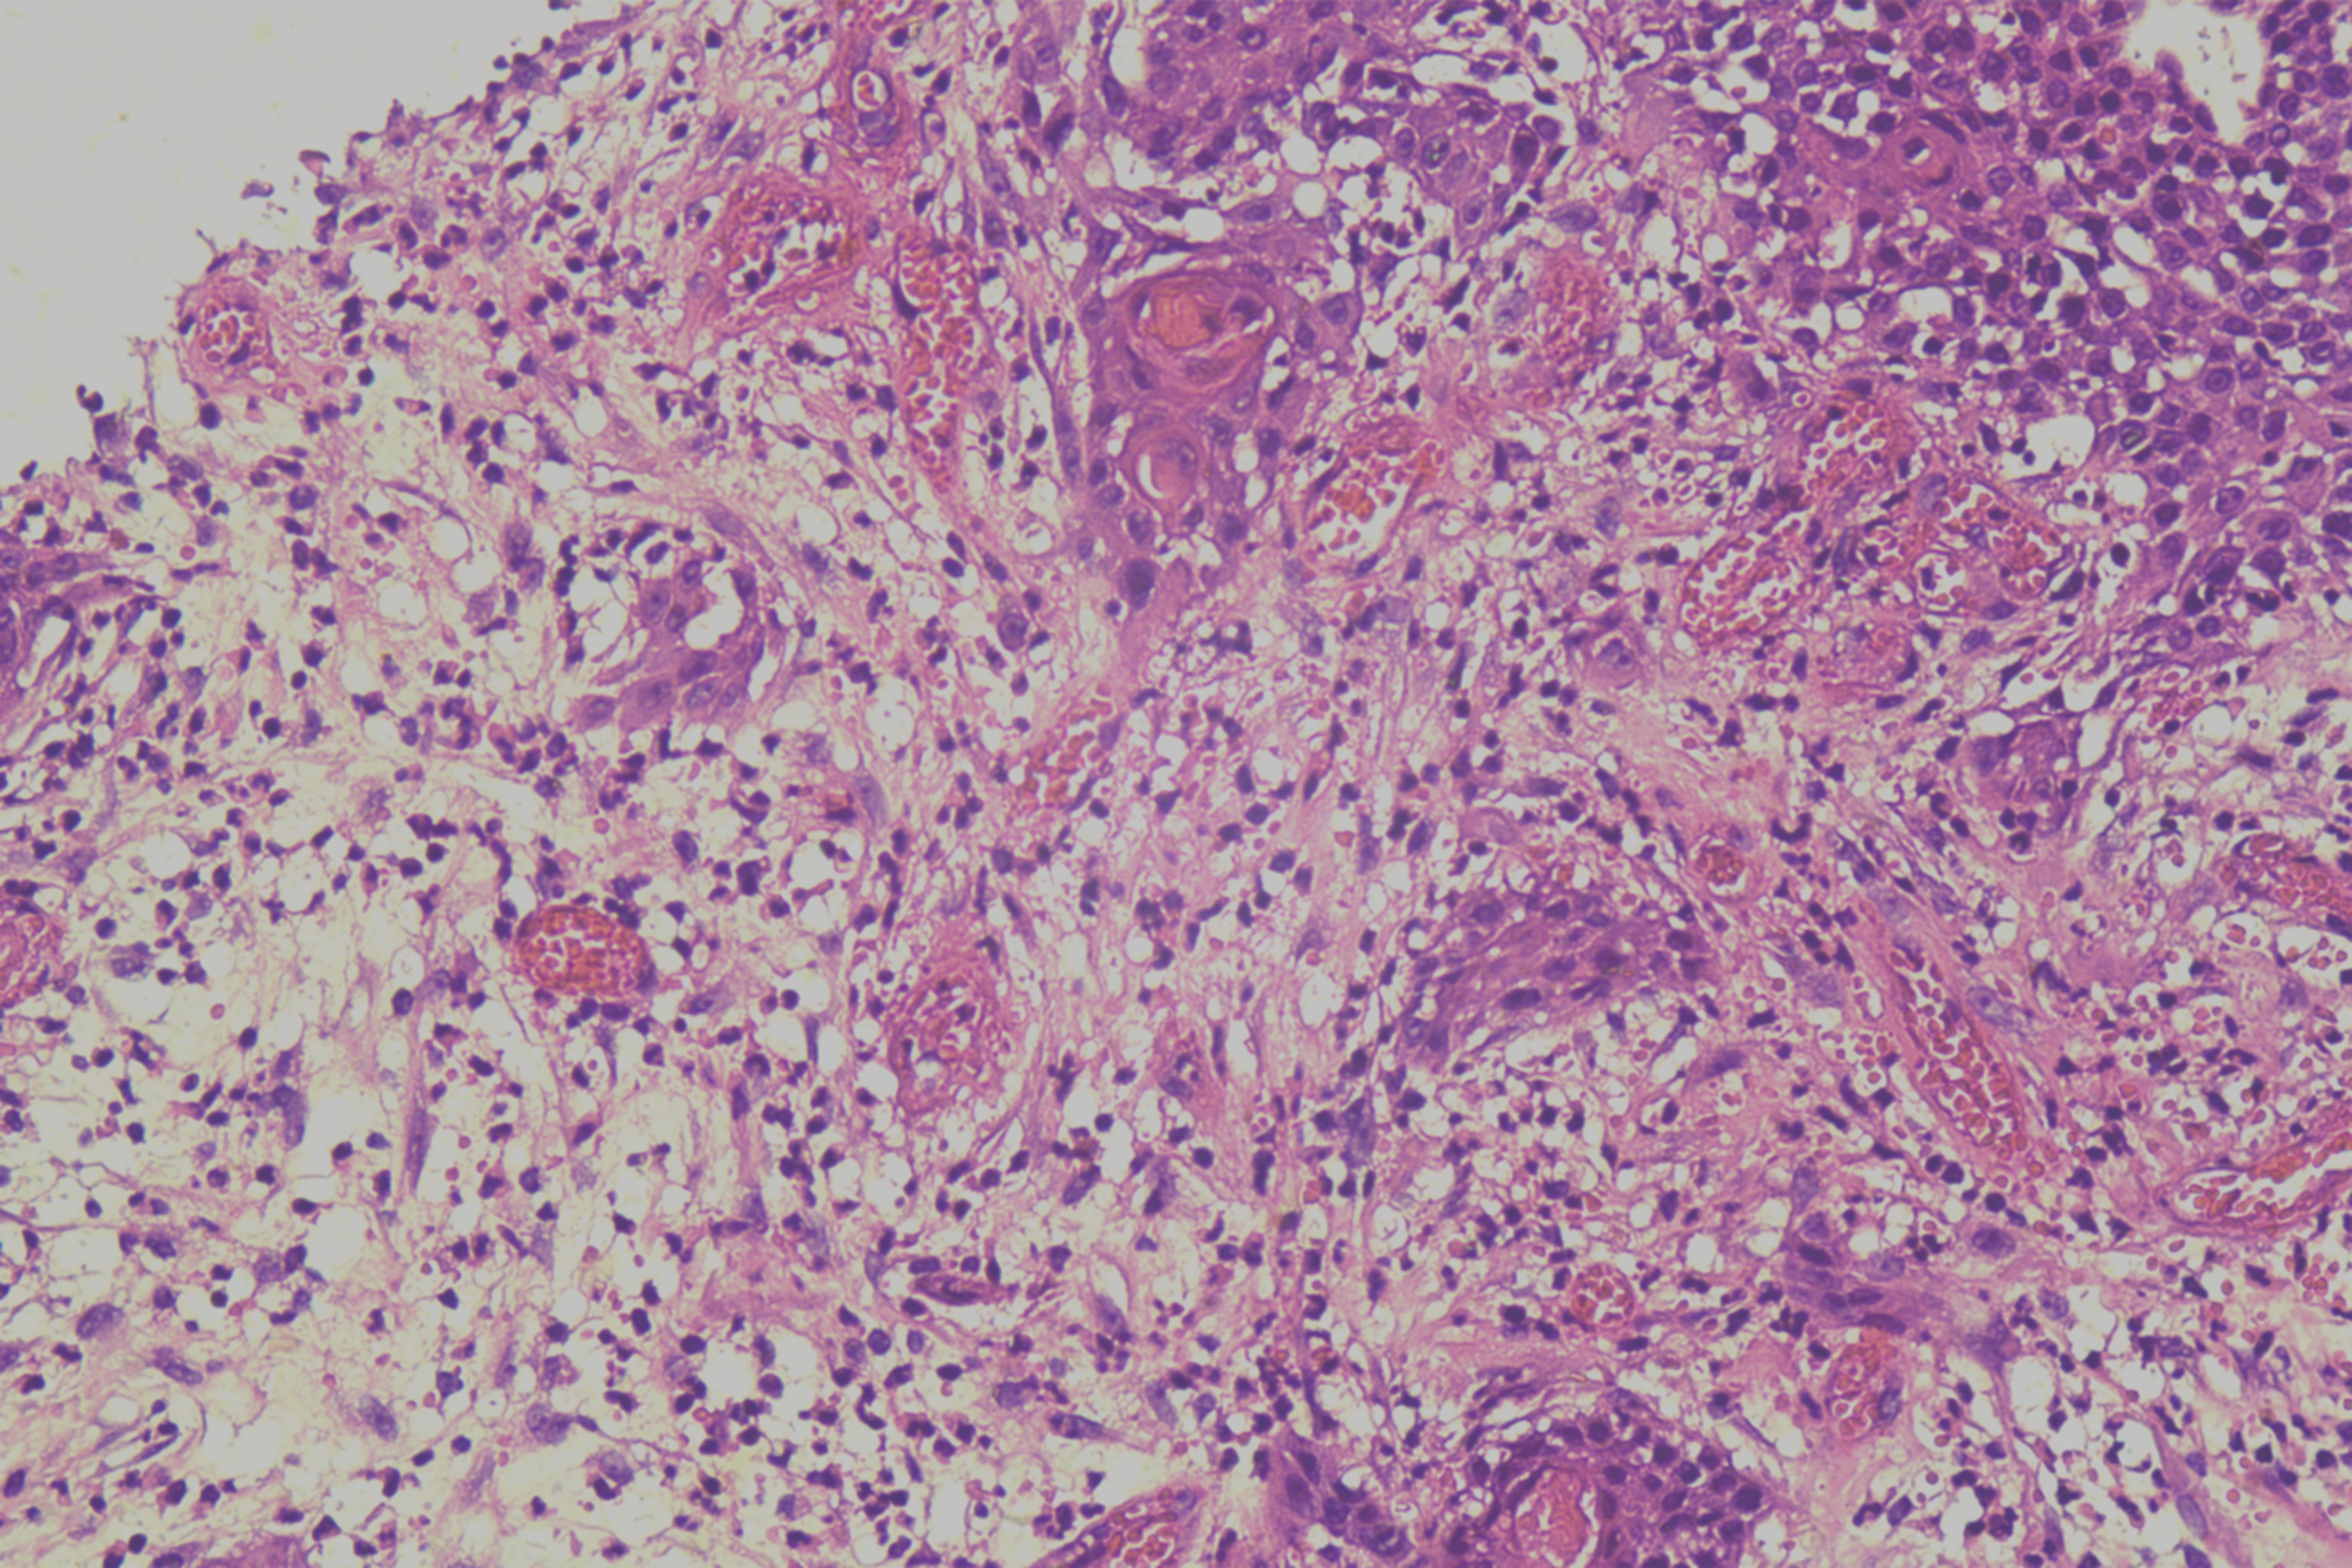

鳞癌?

性别

男

年龄

68岁

头皮肿物20年,包块逐渐增大,反复破溃

头皮肿物(局部活检)

1.5*1*0.3cm灰红碎组织一堆

考虑:基底细胞癌